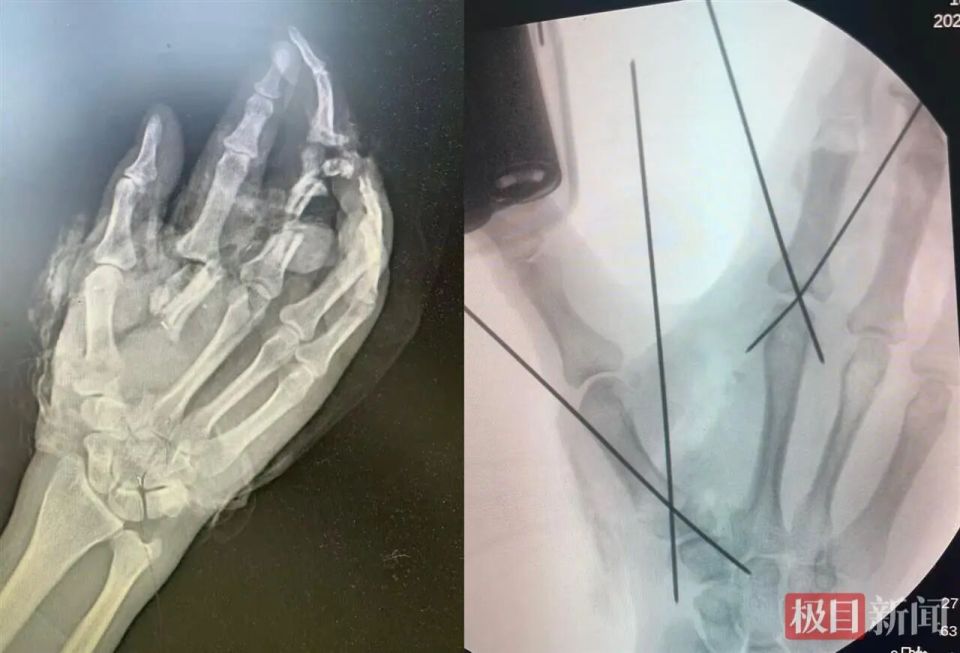

患者手术前后影像图对比

10月底的一个周末下午4时许,陈焱在病区值班时突然接到急诊通知,一位男性工人右手被机器绞伤,手掌及多指离断,情况危机。“患者做工时戴着手套,来的时候右手也是被包着的,但血流不止,急诊通过X光片初步探查了受伤情况。”陈焱回忆,X光片显示孙先生右手第1、2掌骨及中指粉碎性骨折,可见明显的骨质缺损和大小不一的多块游离骨块。

“把完好的部分‘挪位置’!”陈焱当机立断,将尚且完整的食指指体转位到中指对应的掌骨上以替代已经毁损的中指,拇指原位再植。同时做虎口成形术,让已经移位的食指能够继续承担他本应有的功能并最大限度保留手掌的外形及抓握力。

显微镜下的操作堪称绣花功夫:拇指需吻合2根神经、1根血管、1根肌腱;移位的食指要和中指对应的关节相固定,神经血管和肌腱相对接;虎口处从患者自身受损组织中修剪皮瓣,旋转缝合以维持手掌开合度,留住右手抓握功能。“手部的神经和血管比笔尖还细,在吻合神经与血管的同时还要将破碎的手掌修剪缝合成原始的模样。”陈焱和张明医师全程仅靠患者残留的组织就地取材完成了手术,最大限度保留了患肢的外观和功能。

当晚10时多,手术结束。术后一周,孙先生的右手拇指、移位后的食指和剩余的2个指体均保持红润饱满,无任何坏死迹象。